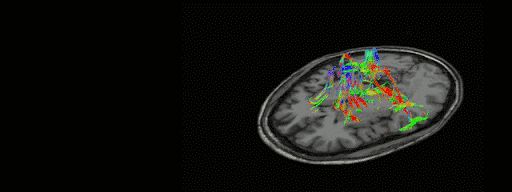

色彩灵动:这张老鼠大脑皮层切片的电子显微镜图像显示了被颜色标记的不同神经元,但这只是一个开始。哈佛大学的杰夫·利希特曼(Jeff Lichtman)说:“我们在研究人类大脑的皮质层,这里的每个神经细胞的任一突触以及连接关系都是可识别的,实在太惊人了。”© Lichtman Lab at Harvard University

“恰恰相反,”他说,“我认为现在我们已经离目标很近了。目前,我们在研究人类大脑的皮质层,这里的每个神经细胞的任一突触以及连接关系都是可识别的,这太惊人了。然而,我不会说完全理解了皮质层,因为那太荒谬了。但这是非常特别的数据,而且很美。从技术的角度来说,你真的可以看到细胞之间是如何连接在一起的,在之前我觉得这根本不可能。”